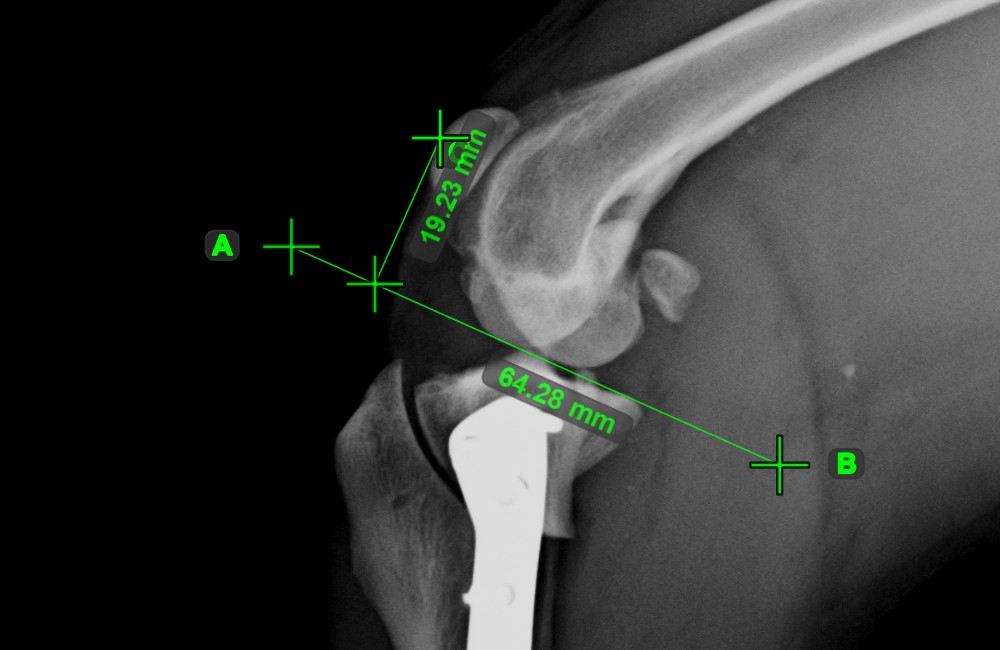

Distance of Line and Point¶

Measure the distance between a line and a specific point on the scene using the Distance of Line and Point tool.

Select the tool from the left toolbar and assign it to one of the available mouse buttons. Start the measurement by selecting an already existing line from the scene. To complete the measurement, place the desired point on the scene or choose from an already exisiting point. The distance between the line and the point will be automatically calculated.

Modify the measurement by moving any of the points using the Select/Move Item tool.